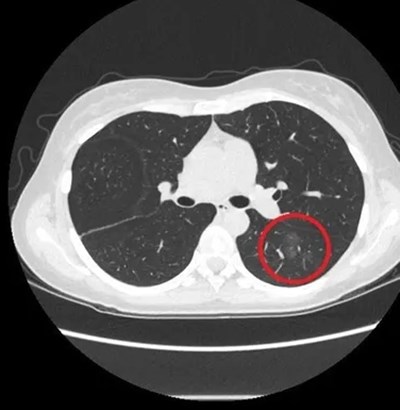

กระทั่งผลปรากฏว่า พบก้อนเนื้อในปอดที่มีลักษณะขุ่นมัวคล้ายฝ้ากระจก เป็นจำนวนมากกว่า 10 ตำแหน่ง และบางตำแหน่งมีขนาดใหญ่กว่า 1 เซนติเมตร หลังจากแพทย์ซักถามประวัติคนไข้โดยละเอียด ทำให้ทราบว่า เธอจำเป็นต้องใช้น้ำยาฟอกขาวสำหรับฆ่าเชื้อเป็นประจำในห้องเรียน แพทย์จึงวินิจฉัยว่า เธอเป็นโรคปอดอักเสบจากสารเคมี ปอดอักเสบที่เกิดจากการสูดดมน้ำยาฟอกขาว ไม่ใช่ก้อนเนื้อในปอดที่เกิดจากมะเร็ง

ต่อมาทางแพทย์ได้ดำเนินการรักษาด้วยยาที่เหมาะสม

และกำชับให้คนไข้รายนี้ลดปริมาณการสูดดมสารฟอกขาว

และหลังจากการรักษาและติดตามผลเป็นเวลา 1 ปี

พบว่าก้อนเนื้อในปอดของเธอหายไปทั้งหมด